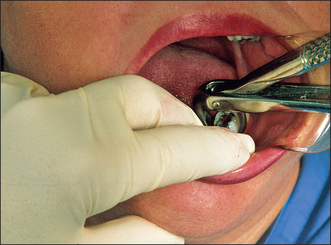

These forceps can be applied to the long axis of anterior teeth, gaining access by the patient opening their mouth fairly widely (Fig. 4.4). However, if one were to attempt to use these forceps on an upper first premolar, there is a risk of traumatizing the lower lip. Forceps for use in the upper jaw further back than the canine have a curve in the beak (Fig. 4.5), which keeps them above the lip when they are in the long axis of the tooth. The beaks of these forceps are also concave on their inner aspect to fit the root of upper premolars.

Fig. 4.5 Application of upper premolar forceps (no. 76).

Note the curve in the beak.